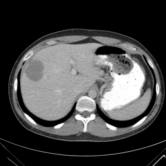

The category discovery clusters employing our LDPO method are found to be more visually coherent and cluster-wise balanced in comparison to the results in [44] where clusters are formed only from text information ( radiology reports). Fig. 4 Left shows the image numbers for each cluster from the AlexNet-FC7-Topic setting. The numbers are uniformly distributed with a mean of 778 and standard deviation of 52. Fig. 4 Right illustrates the relation of clustering results derived from image cues or text reports [44]. Note that there is no instance-balance-per-cluster constraints in the LDPO clustering. The clusters in [44] are highly uneven: 3 clusters inhabit the majority of images. Fig. 5 shows sample images and top-10 associated key words from 4 randomly selected clusters (more results in the supplementary material). The LDPO clusters are found to be semantically or clinically related to the corresponding key words, containing the information of (likely appeared) anatomies, pathologies (e.g., adenopathy, mass), their attributes (e.g., bulky, frontal) and imaging protocols or properties.

Next, from the best performed LDPO models in Table 2, AlexNet-FC7-Topic has Top-1 classification accuracy of 0.8109 and Top-5 accuracy 0.9412 with 270 formed image categories; AlexNet-FC7-ImageNet achieves accuracies of 0.8099 and 0.9547, respectively, from 275 discovered classes. In contrast, [44] reports Top-1 accuracies of 0.6072, 0.6582 and Top-5 as 0.9294, 0.9460 on 80 text only computed classes using AlexNet [27] or VGGNet-19 [47], respectively. Markedly better accuracies (especially on Top-1) on classifying higher numbers of classes (being generally more difficult) highlight advantageous quality of the LDPO discovered image clusters or labels. This means that the LDPO results have rendered significantly better performance on automatic image labeling than the most related previous work [44], under the same radiology database. After the subjective evaluation by two board-certified radiologists, AlexNet-FC7-Topic of 270 categories and AlexNet-FC7-ImageNet of 275 classes are preferred, out of total six model-encoding setups. Interestingly, both CNN models have no deep feature encoding built-in and preserve the gloss image layouts (capturing somewhat global visual scenes without unordered FV or VLAD encoding schemes [9, 8, 21].).

The final trained CNN classification models allow to compute the pairwise category similarities or affinity scores using the CNN classification confusion values between any pair of classes (Sec. 3.5). Affinity Propagation algorithm is called recursively to form a hierarchical category tree. The resulted category tree has (270, 64, 15, 4, 1) different class labels from bottom (leaf) to top (root). The random color coded category tree is shown in Fig. 6. The high majority of images in the clusters of this branch are verified as CT Chest scans by radiologists. Enabling to construct a semantic and meaningful hierarchy of classes offers another indicator to validate the proposed LDPO category discovery method and results. Refer to the supplementary material for more results. We will make our trained CNN models, computed deep image features and labels publicly available upon publication.